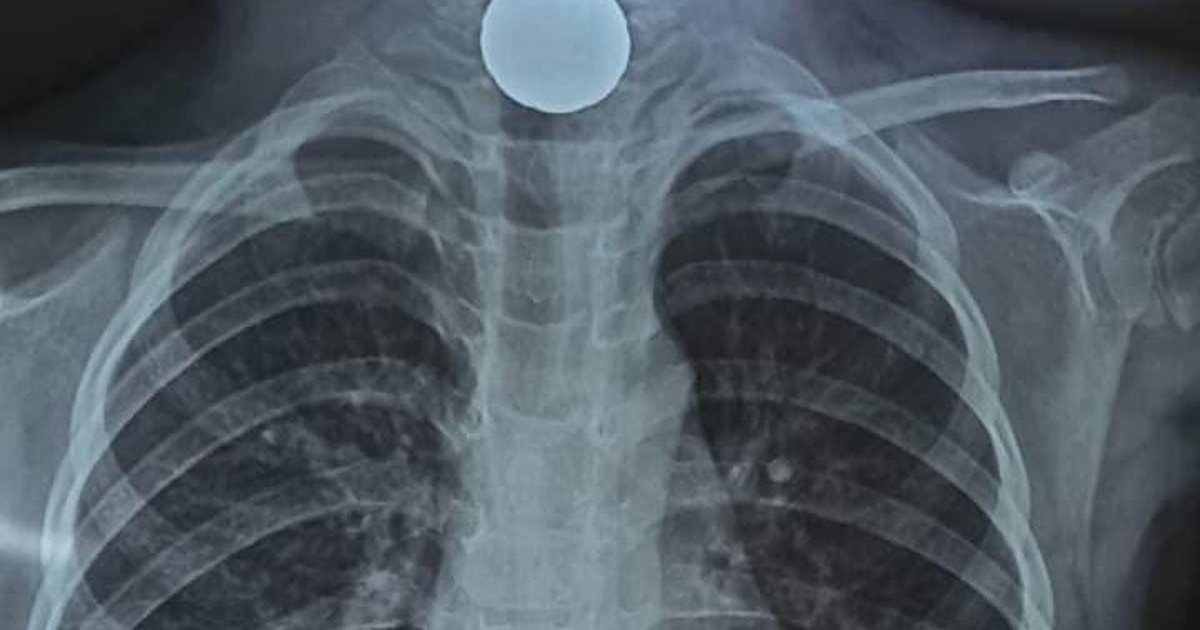

Một bé gái 5 tuổi ở Hà Tĩnh không may nuốt đồng xu vào thực quản, phải nhập viện để các bác sĩ nội soi để gắp dị vật ra ngoài.